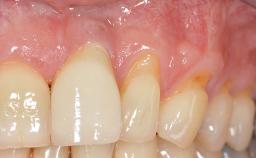

Soft-Tissue Augmentation Using a Porcine-Derived Collagen Matrix to Correct a Labial Soft-Tissue Defect Following Extraction of a Maxillary Incisor

In this case, Shakeel Shahdad employs a two-layer matrix to repair a soft-tissue defect in a post-extraction healed site prior to implant placement with simultaneous guided bone regeneration. This approach resulted in a gain of keratinized peri-implant mucosa with optimal shade and texture. Soft-tissue defects are often encountered prior to implant placement and may result in deficient attached keratinized mucosa, which unless corrected will yield less than ideal esthetic outcomes. The presence of keratinized mucosa has been proposed as one of the prognostic factors for the survival of dental implants (Adell and coworkers 1986) with reported greater reductions in gingival and plaque indices after increasing the width of keratinized mucosa by soft-tissue augmentation (Giannobile and coworkers 2018; Thoma and coworkers 2018).